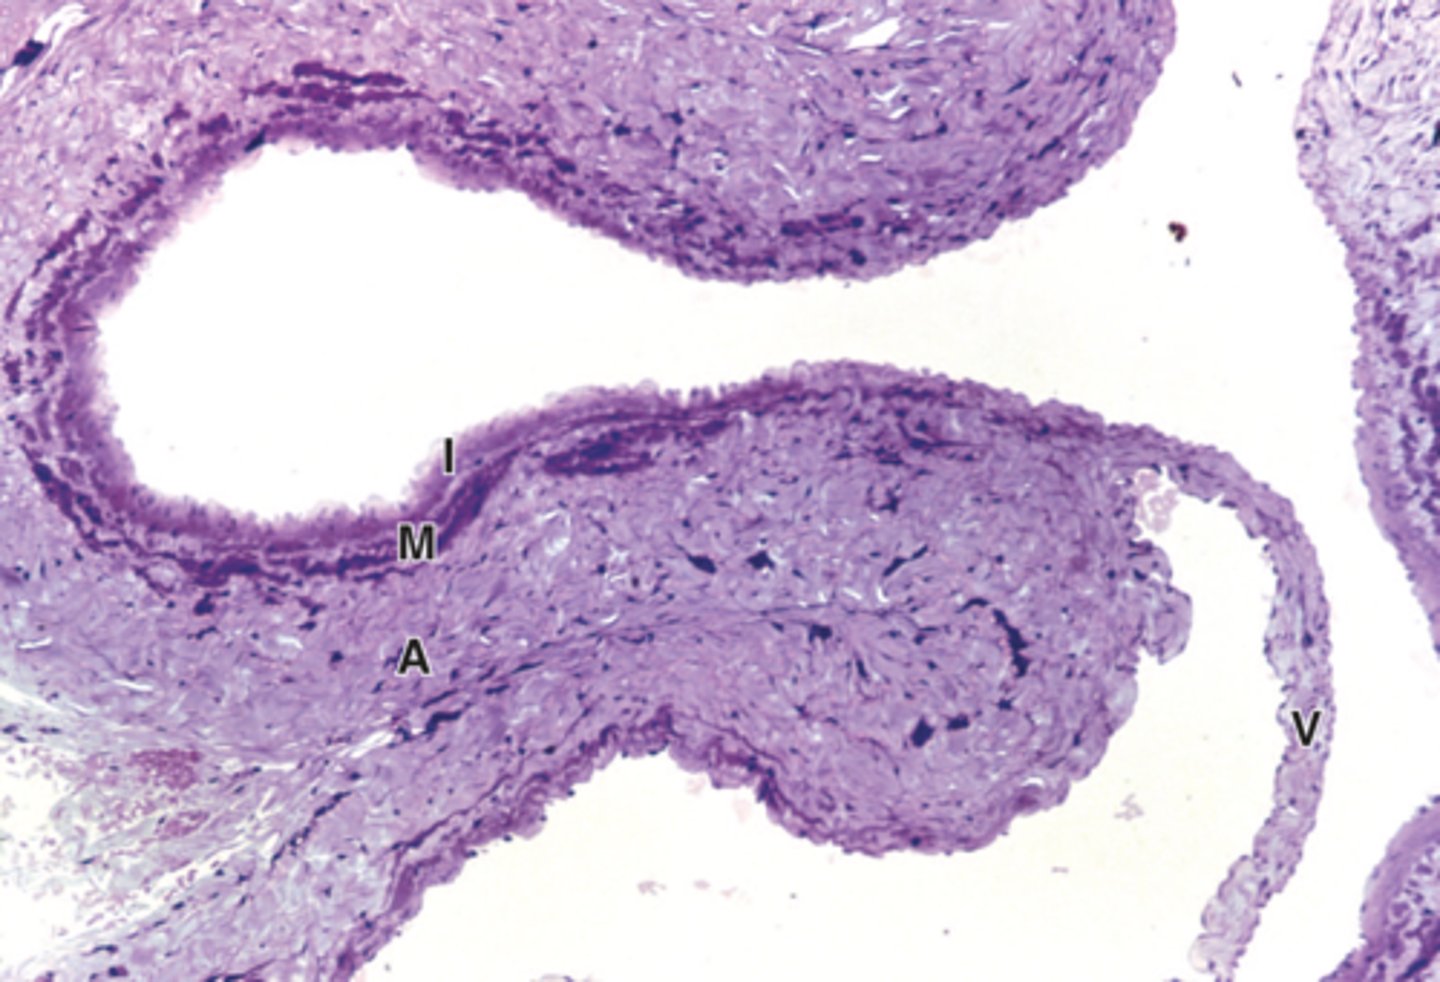

large vein

I: tunica intima

M: tunica media

A: tunica adventitia

V: valve

ID tissue. What are each of the letters?large vein